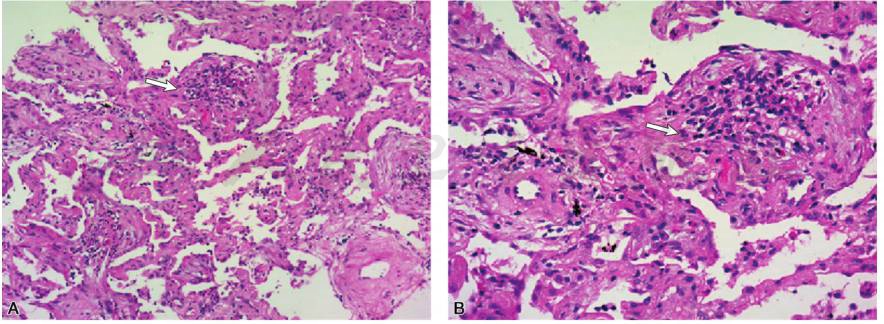

CT引导下经皮肺穿刺活检送病理(2017-05-12):(左肺)送检组织内肺泡腔机化性改变,肺泡间隔增宽,伴纤维化,见少量淋巴细胞和嗜酸性粒细胞浸润,肺泡结构完整,符合间质性肺炎改变(图2)。

图2 肺穿刺病理(A:×100;B:×200):(左肺)送检组织HE染色可见肺泡间隔增宽,伴纤维化,见少量炎症细胞浸润,部分肺泡腔可见机化性改变(白箭),符合间质性肺炎